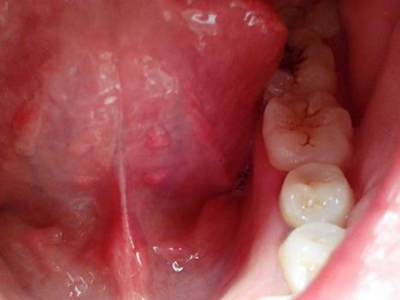

口腔尖锐湿疣是由人乳头瘤病毒感染引起的发生于口腔黏膜的性传播疾病,主要由HPV6、11等型引起。引起尖锐湿疣的某些HPV亚型与癌的发生有关,表现为疣状结节。口腔尖锐湿疣多由口交感染引起,好发生于性活跃的青、中年。

口腔尖锐湿疣好发于舌、牙龈、腭等部位,表现为单个或多个无痛性的疣状结节,有蒂或无蒂,可逐渐增大或融合,形成菜花状、乳头状赘生物,颜色呈肉色或苍白色,患者可有异物感。